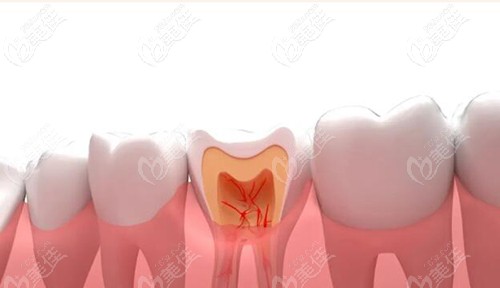

齲壞后補了牙的牙齒還會爛到牙髓么?爛透了的話要做根管治療嗎?

很多人都比較好奇齲壞補牙后牙齒還會爛到牙髓嗎?如果一旦觸碰到牙髓需要做根管治療嗎?今天我們逐一解答!

除了牙疼外,蛀牙還能怎么確定爛到神經了? b1605 G0 V0

別小看一顆小小的蛀牙,它可會導致傷到牙神經讓牙爛掉,那么蛀牙怎么確定爛到神經了呢?除了牙疼外還能這么判斷。